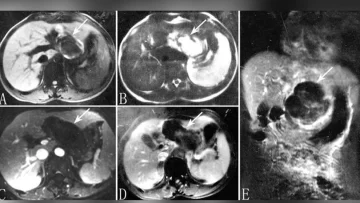

Entonces se procedió a hacerle un ecografía que reveló que había un bebé en su hígado.

Tenía una versión extremadamente rara de un embarazo ectópico, en el que "un óvulo fertilizado se implanta y crece fuera de la cavidad principal del útero", de acuerdo con los datos de la Clínica Mayo.

Sin embargo, el caso de esta paciente era aún más raro, ya que el embrión "acabó viajando hasta el hígado, donde se implantó", señaló el médico.